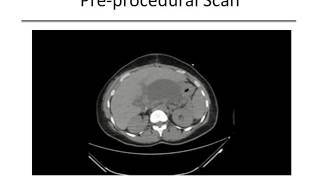

Image Guided Percutaneous Drainage of Abnormal Abscesses and Fluid video

Image-Guided Percutaneous Drainage of Abnormal Abscesses and Fluid

Image-Guided Percutaneous Drainage of Abnormal Abscesses and Fluid Image-Guided Percutaneous Drainage of Abdominal Abscessed and Fluid Collections

Image-Guided Percutaneous Drainage of Abnormal Abscesses and Fluid

Image-Guided Percutaneous Drainage of Abnormal Abscesses and Fluid Image-Guided Percutaneous Drainage of Abdominal Abscessed and Fluid Collections